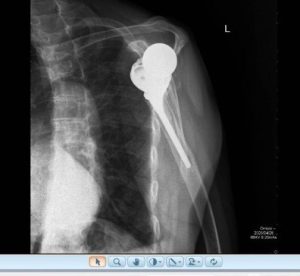

Segundo caso de utilização do sistema VIP Arthrex numa revisão de prótese invertida por loosening asséptico secundário a notching inferior.

Planeamento pre operatório após remoção de implantes anteriores. O sistema permite remover implantes e simular várias opções de dimensão e posicionamento quer da baseplate e glenosfera bem como do componente úmeral. Obtivemos um resultado em termos de mobilidade passiva no intra operatório exatamente igual ao planeado. Trata-se de uma inovação incrível na cirurgia de precisão, útil sobretudo em revisões complexas. O grupo do ombro da Luz Oeiras a inovar mais uma vez.